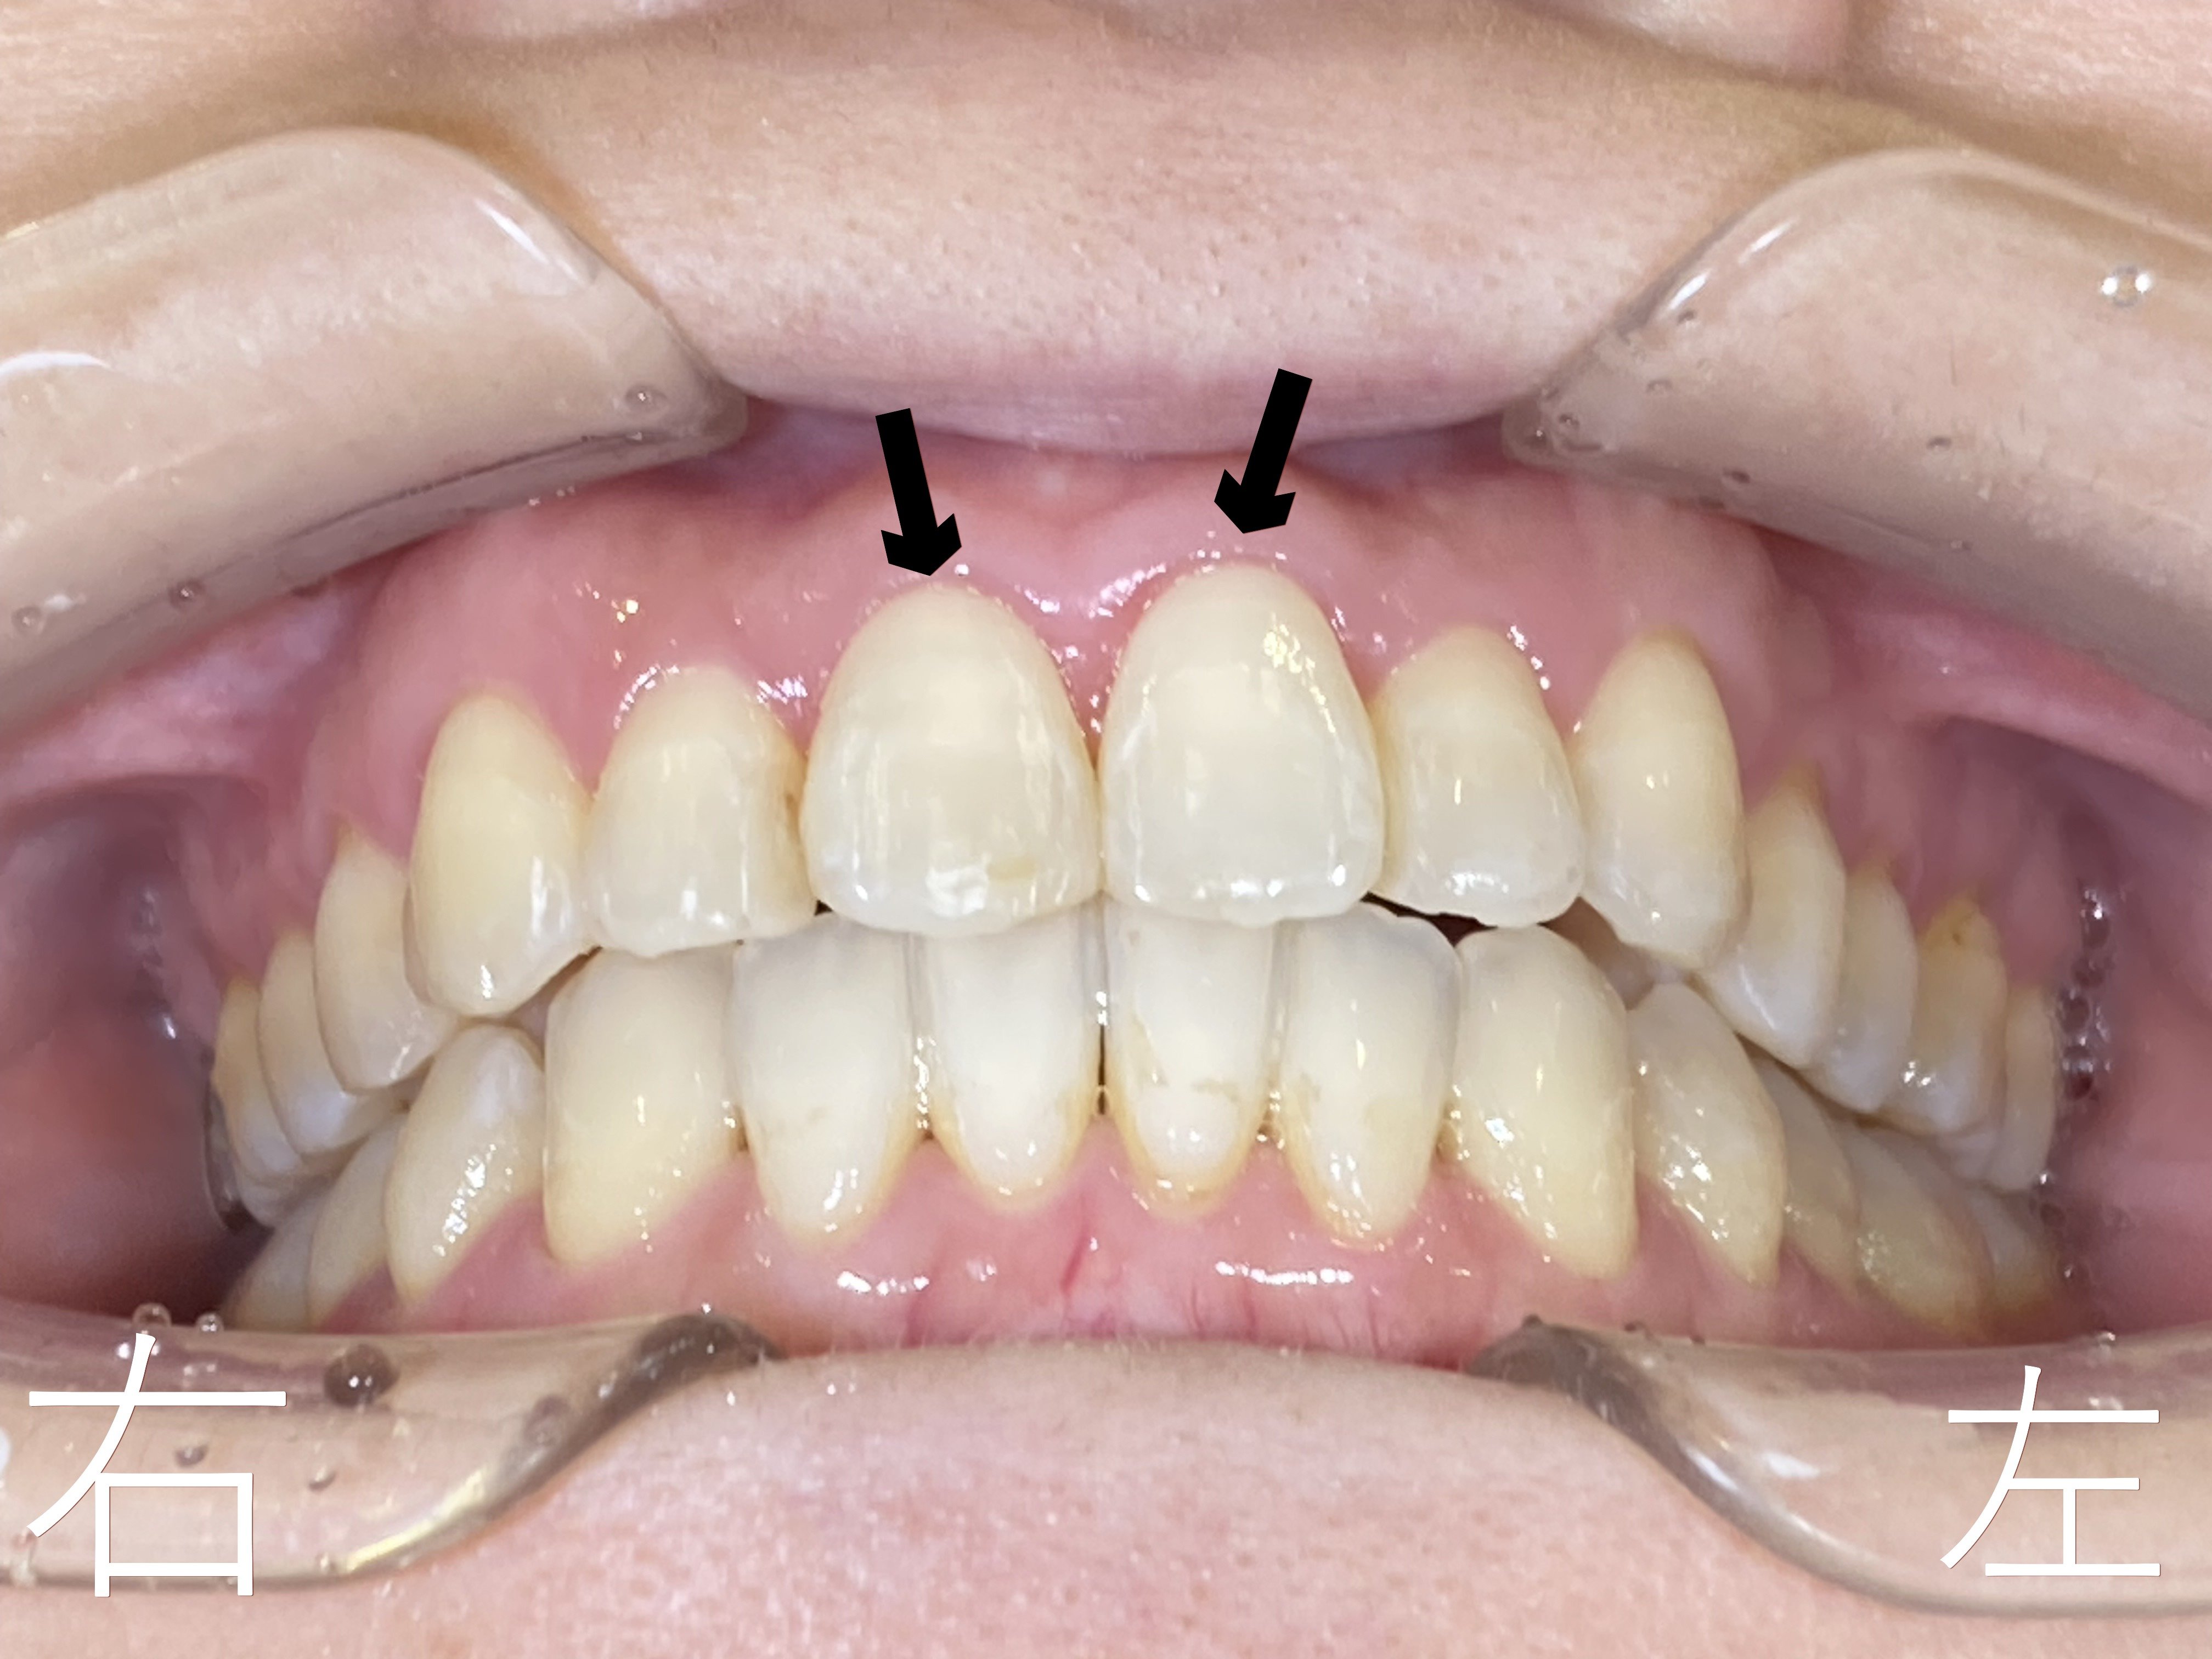

上顎左右前歯部(黒色矢印の歯)のゆがみ【叢生】が確認できます。

上記は上下ともセラミック製のブラケット(ボタン)を装着した正面観です。

上記は8か月後の正面からみた写真です。上顎中切歯(黒色矢印)をご覧ください。

矯正前にあったゆがみ【叢生】が解消されています。